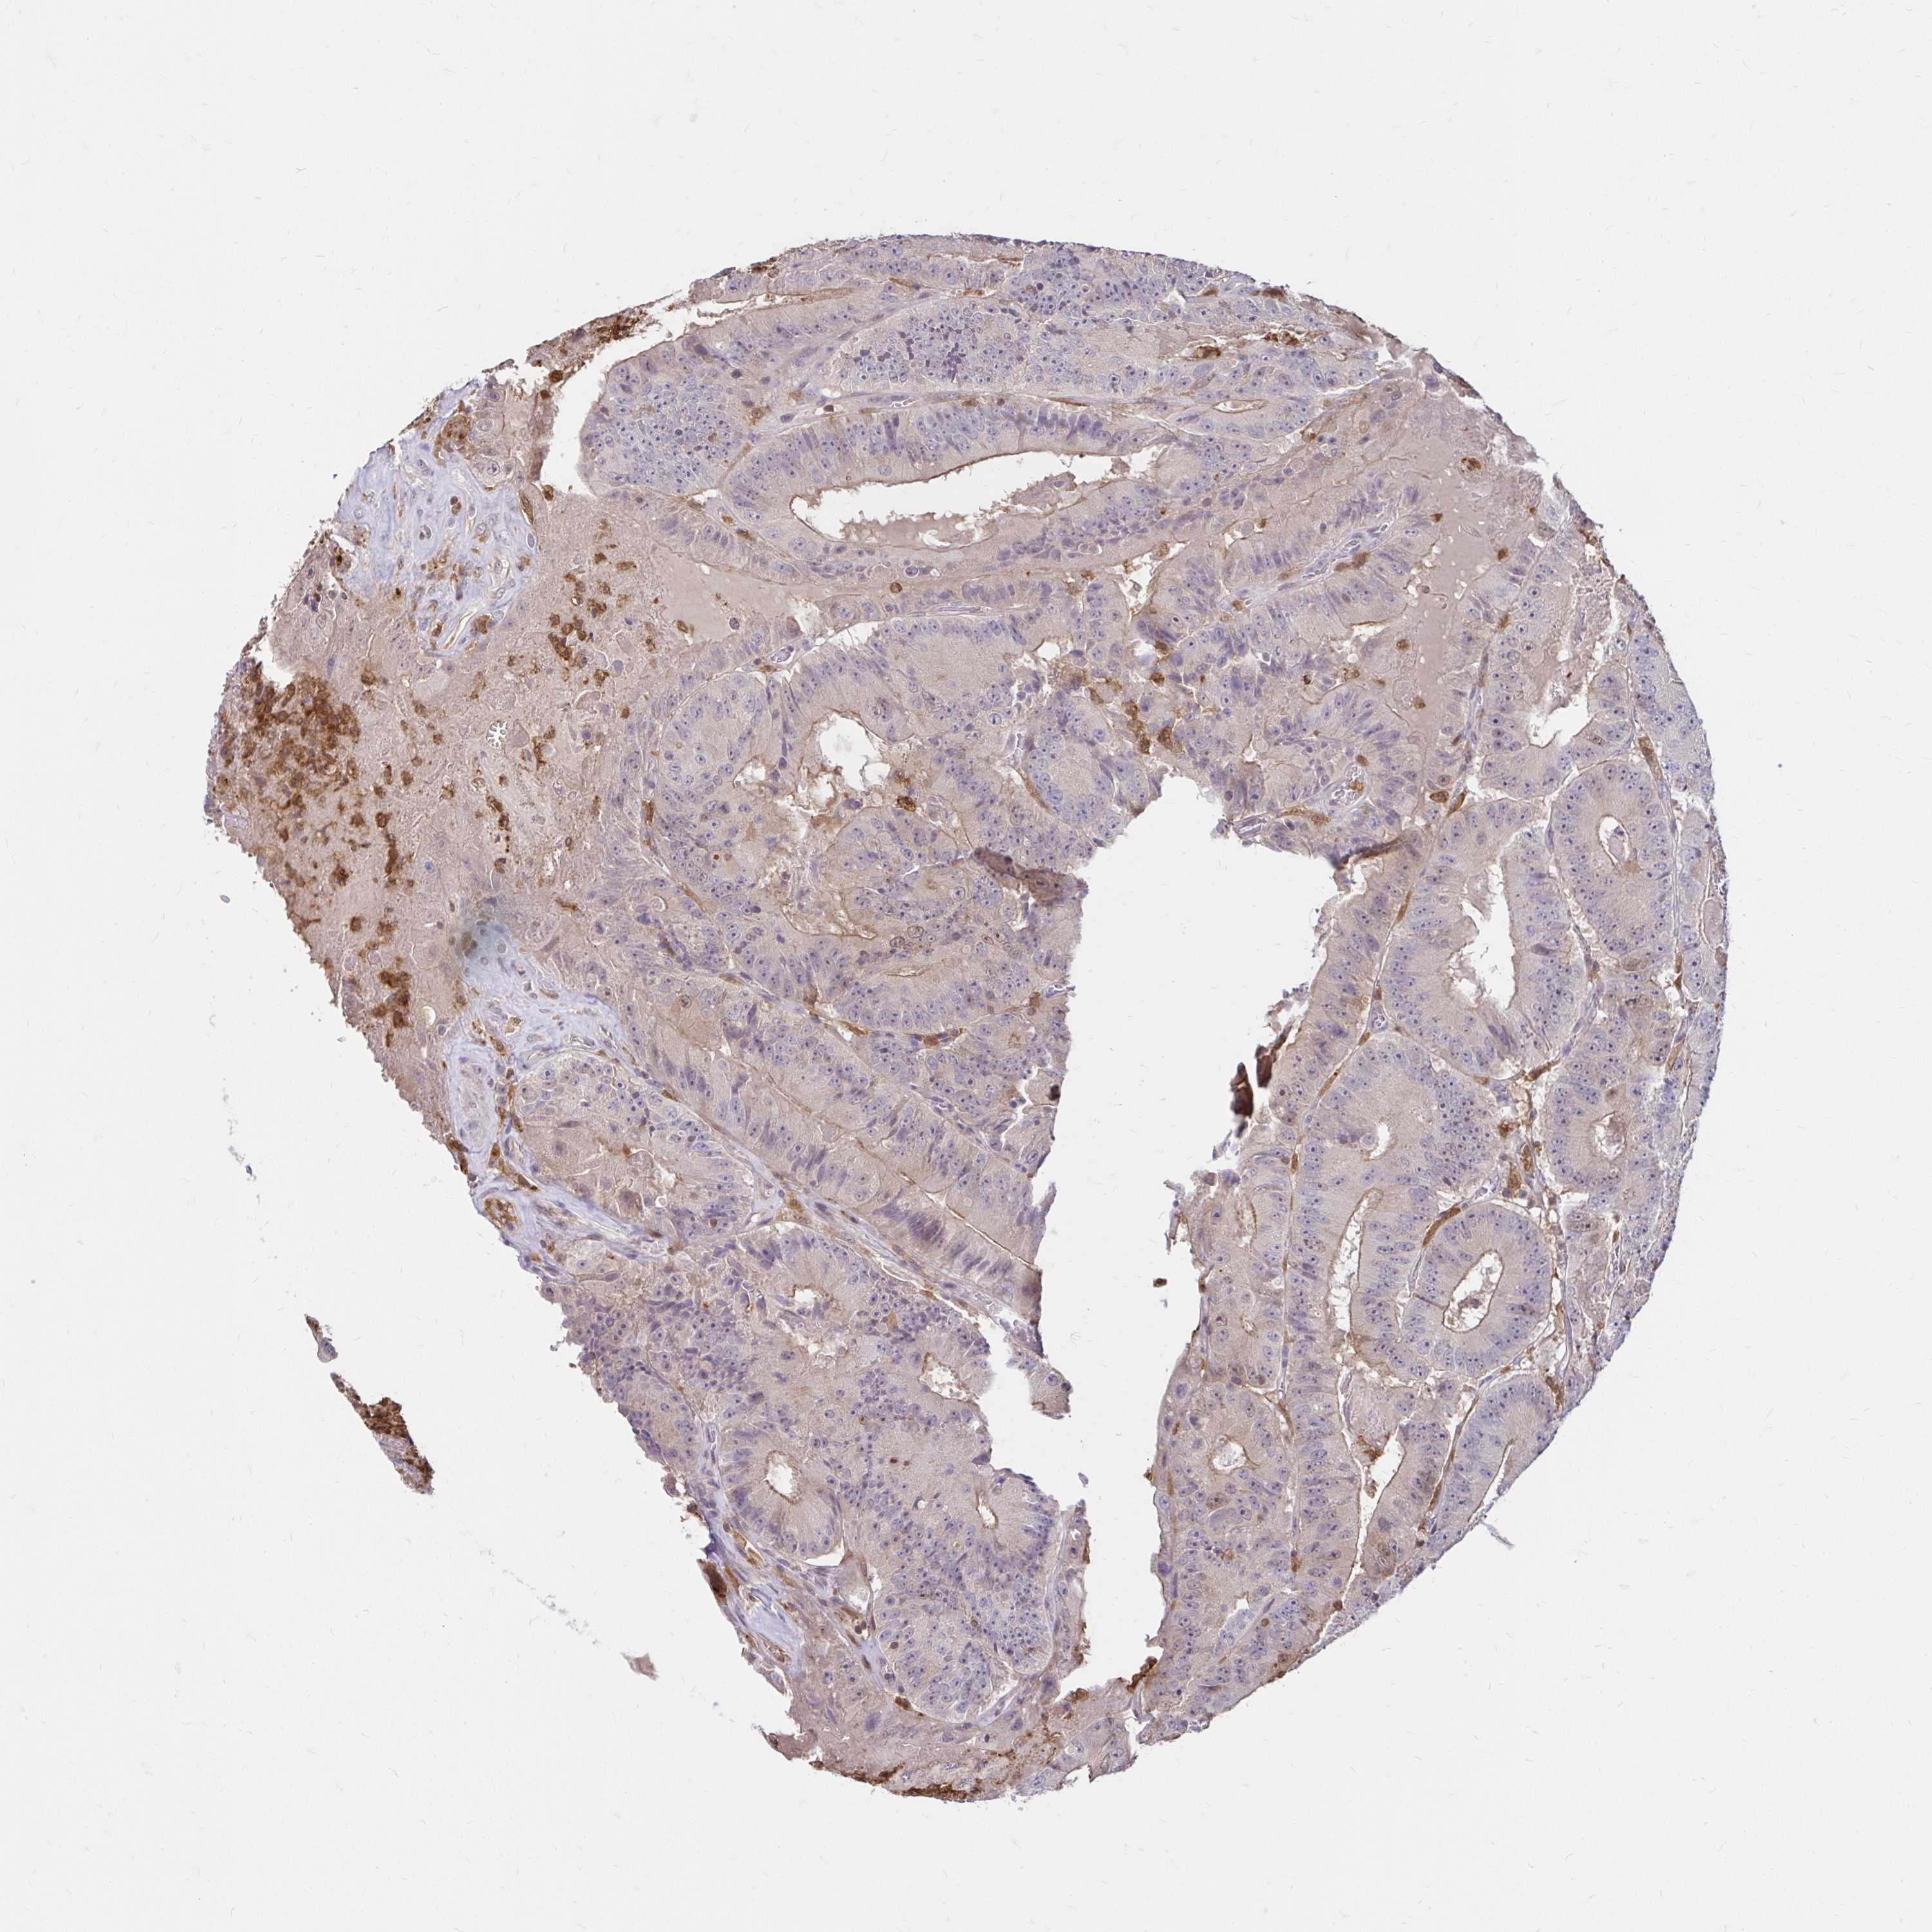

CANCER COLORECTAL CANCER Show tissue menu

Colorectal cancer

Human cancer